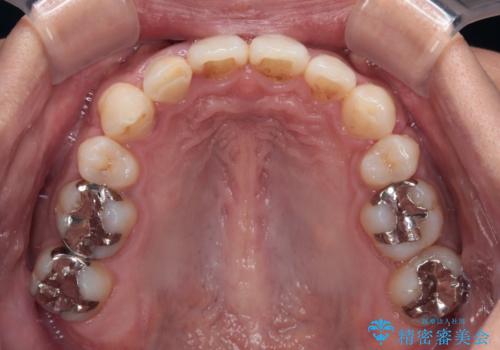

八重歯による叢生は著しく、それにより上顎の正中が大きく右にずれている状態でした。

口元の突出感は感じていなかったことと、奥歯の咬み合わせを考慮し、上顎のみ左右の第一小臼歯を抜歯してワイヤー装置にて矯正治療を行うこととしました。

補助装置を併用することで効率的に八重歯や正中位置の改善を達成することができました。